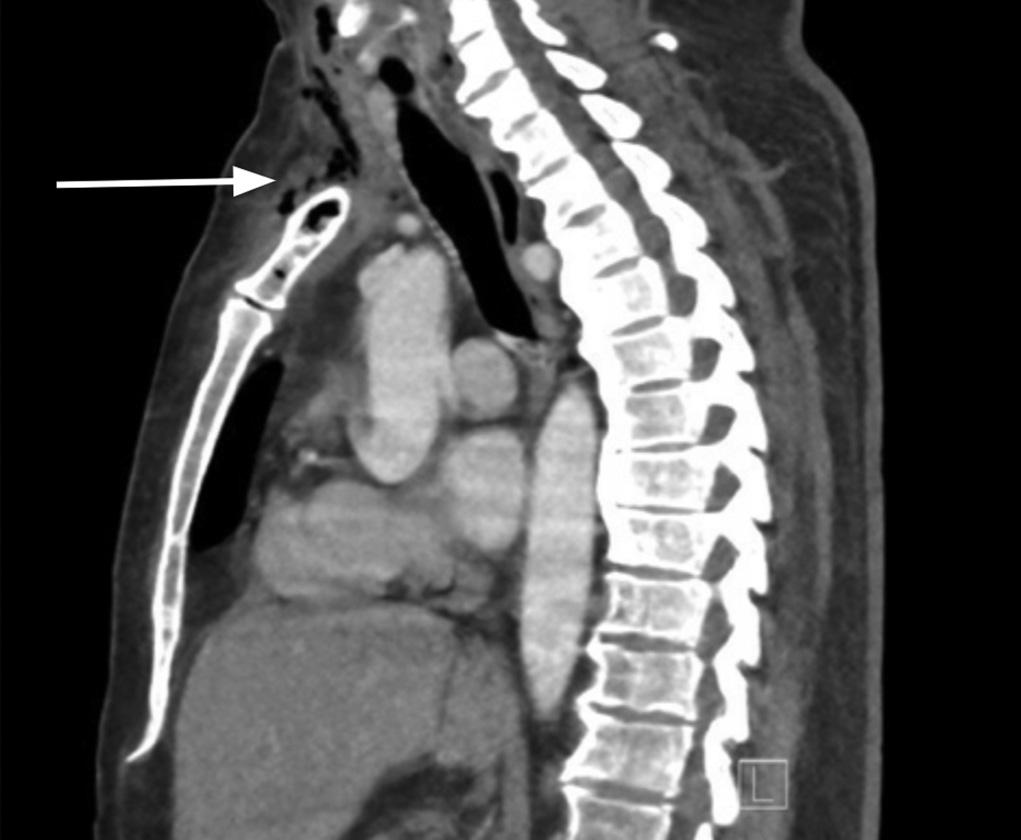

Emergentcomputedtomographyoftheabdomenand pelvisrevealedalargeleftretroperitonealandperitoneal hematomasecondarytoleftRAArupture,aswellasconcern fordevelopingsplenicinfarctsintheleftlowerrenalpole (Image).Thepatientwastakenemergentlytotheoperating room(OR)forexploratorylaparotomywithintwohoursof EDarrival.Sheunderwentsuprarenalcross-clampingwith repairoftheleftrenalarteryandligationofrenalvessels.She returnedtotheORtwodayslaterforleftnephrectomyand abdominalclosure.Shewasextubatedandtransferredtothe floor.Shewasdischargedhometwodayslaterin goodcondition.